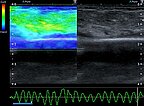

In ultrasound elastography, the mechanical stiffness of the tumor can be color-coded (left image), with the corresponding B-scan on the right. In color coding, hard tissue is shown in blue, medium-hard tissue in green and soft tissue in red. The tumor itself is medium-hard to slightly softer (green) than the surrounding tissue (blue).